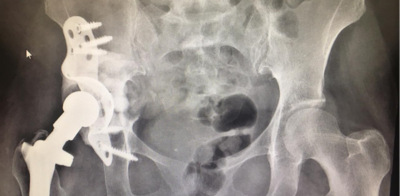

جراحة استبدال مفصل الورك هي عملية تستخدم لاستبدال مفصل الورك التالف بأجزاء اصطناعية اصطناعية جديدة ومتينة تحاكي المفصل الأصلي، ومن الضروري الحفاظ على سلامة المفصل الجديد بعد إجراء العملية.

- زيارة جراح العظام بشكل دوري لمتابعة الاختبارات والأشعة السينية حتى ولو كان مفصل الورك المستبدل يبدو جيداً.